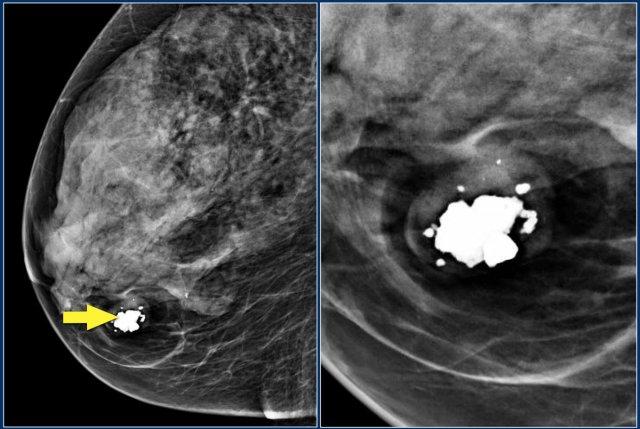

Đây là hình ảnh một khối tăng tỷ trọng với hình dạng không đều và bờ tua gai.

Lưu ý hiện tượng co rút da khu trú.

Trường hợp này được phân loại BI-RADS 5 và được xác nhận là ung thư biểu mô tuyến vú xâm lấn.